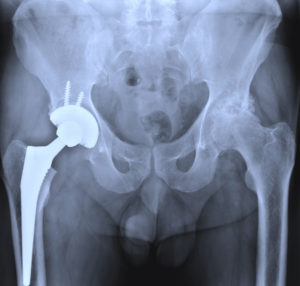

- Defective Medical Devices

- Stryker Hip